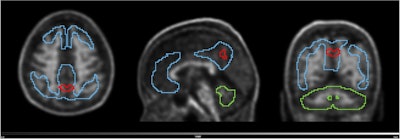

Volume with higher baseline signal for N1 accumulators and N1 non-accumulators of amyloid (red line) overlayed on the scan of an N1 accumulator (MNI space). Grey scale shows SUVR range. Blue line shows the Centiloid target region and the green line shows the reference region (whole cerebellum).European Journal of Nuclear Medicine and Molecular Imaging

Volume with higher baseline signal for N1 accumulators and N1 non-accumulators of amyloid (red line) overlayed on the scan of an N1 accumulator (MNI space). Grey scale shows SUVR range. Blue line shows the Centiloid target region and the green line shows the reference region (whole cerebellum).European Journal of Nuclear Medicine and Molecular Imaging

To identify the region highlighted in red, an amyloid-negative population (at baseline) with subjective cognitive decline was assessed with a voxel-based analysis using standardized uptake value ratios (SUVRs). Then, the baseline SUVR images of amyloid accumulators versus nonaccumulators were compared. Amyloid accumulation status was defined using the Centiloid method and with a five-year follow-up, Kolinger said.

The results showed that accumulators exhibited higher baseline SUVR in the red-marked region, which corresponds to part of the precuneus, a brain area known to play a role in early Alzheimer's disease. This region overlaps with the Centiloid target region (shown in blue), underscoring the potential of this approach to enhance preclinical Alzheimer's disease assessment, Kolinger added.